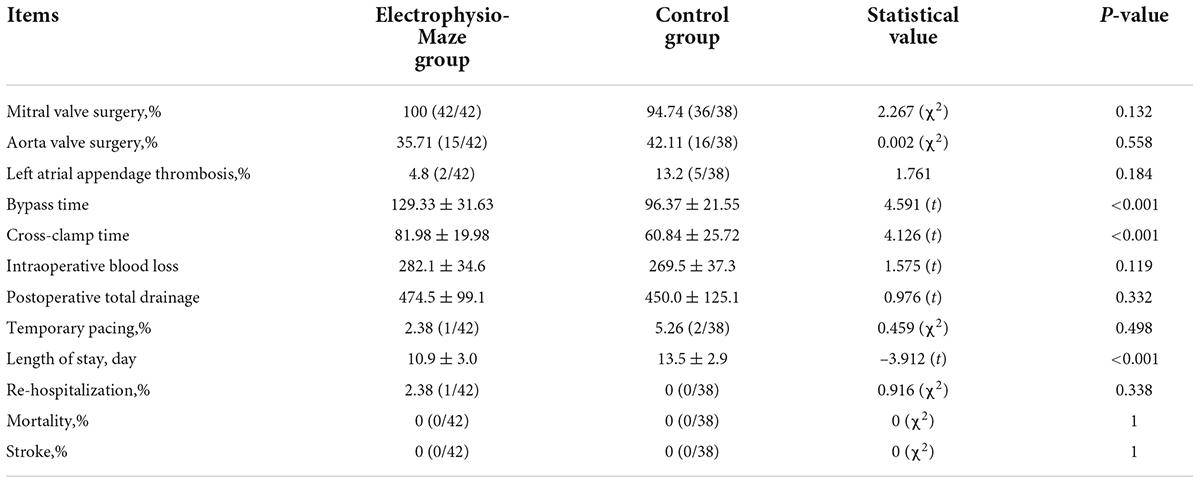

Totally, 42 patients were enrolled into the Electrophysio-Maze group, and 38 patients were enrolled into control group. Between two groups, there were no difference in sex, age, duration of AF, long-standing AF percent, Euroscore II score, hypertension, coronary heart disease, preoperative cardiovascular accident, preoperative TIA, left atrial diameter, right atrial diameter, left ventricular diastolic diameter, right ventricular diastolic diameter, ejection fraction, and the use of antiarrhythmic drugs (Table 1).

Comparison of perioperative characteristics between two groups

There were no statistical difference in type of valve operation (percent of mitral valve and aorta valve), left atrial appendage thrombosis and temporary pacing, intraoperative blood loss, and postoperative total drainage volume between two groups. No patient was implanted with a permanent pacemaker, and no patient died or underwent stroke during hospitalization in both groups. Compared with control group, patients in the Electrophysio-Maze group underwent longer bypass time and cross-clamp time. In the Electrophysio-Maze group, a patient underwent rehospitalization due to chest wound infection and recovered after debridement, but there are no statistical differences in rehospitalization between two groups. Interestingly, Electrophysio-Maze can significantly shorten the length of hospitalization stay (Table 2).